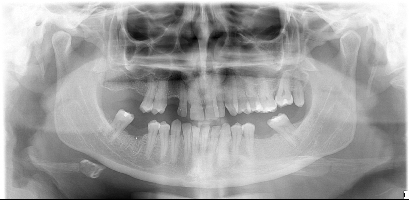

Buonasera scrivo per avere maggiori dettagli (opinioni specialistiche )sulla mia situazione non facile é da tempo che avverto dolore a dei dent,i caso strano la notte dormo specifico non mi sveglio per il dolore che al contrario mi accompagna nell'arco della giornata ad intervalli più o meno intensi inserisco la mia ortopanoramica . Saluti

chicca.jpg

[ 51.31 KiB | Osservato 2027 volte ]